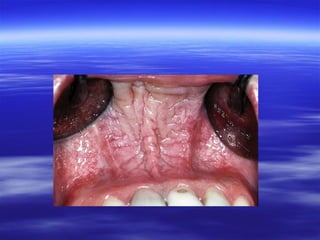

:Denture-induced Stomatitis

 Asymptomatic erythema sharply limited to

the area of mucosa occluded by a wellfitting upper denture or even an orthodontic

plate.

 Similar inflammation is not seen under the

more mobile lower denture which allows a

relatively free flow of saliva beneath it.

 Angular stomatitis is frequently associated

and may form the chief complaint.